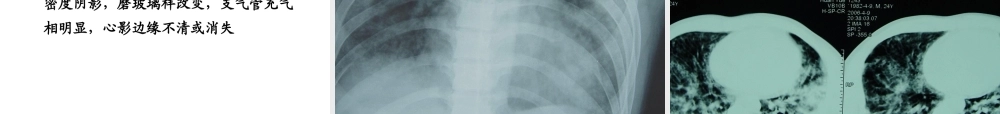

AcuteRespiratoryDistressSyndromeAcuteRespiratoryDistressSyndromeAcuteRespiratoryDistressSyndromeAcuteRespiratoryDistressSyndrome教学内容ALD/ARDS呼吸支持技术MODS/SIRS第一节第一节ALI/ARDSALI/ARDS重点ALI/ARDS概念ALI/ARDS病因ALI/ARDS临床表现ALI/ARDS诊断ALI/ARDSALI/ARDS治疗治疗病例男,25岁“肾病综合征”病史5年,长期口服激素发热、咳嗽10天,气促2天入住肾内科,抗心衰无效HR150次/分R45次/2006.11.24(一)概念急性进行性缺氧性呼吸衰竭急性进行性缺氧性呼吸衰竭各种肺内外原因(各种肺内外原因(排出心脏排出心脏))呼吸窘迫低氧血症(呼吸窘迫低氧血症(ALI/ARDSALI/ARDS))肺微血管通透性肺微血管通透性↑↑肺透明膜形成肺透明膜形成肺顺应性肺顺应性↓↓、、V/QV/Q失调失调全世界对ARDS的认知不容乐观2005年的研究显示,ARDS发病率分别在每年79/10万和59/10万严重感染时ARDS患病率可高达25%-50%,大量输血可达40%,多发性创伤达到11%-25%,而严重误吸时,患病率也可达9%-26%。国际荟萃分析显示,ARDS患者的病死率在50%左右。中国上海市15家成人ICU2001年3月至2002年3月ARDS病死率也高达68.5%。表表1ALI/ARDS1ALI/ARDS发病危险因素发病危险因素直接因素直接因素间接因素间接因素肺或胸部挫伤肺或胸部挫伤败血症,脓毒症败血症,脓毒症误吸误吸严重的非胸部创伤严重的非胸部创伤淹溺淹溺休克休克严重肺部感染严重肺部感染大量输血(输液)大量输血(输液)吸入有毒气体吸入有毒气体重症胰腺炎重症胰腺炎氧中毒氧中毒药物过量药物过量脂肪栓塞脂肪栓塞体外循环体外循环肺移植再灌注损伤肺移植再灌注损伤DIC机制未明直接致炎因子作用炎症细胞/至炎因子间接作用大量炎性介质(炎性细胞因子、过氧化物、白三烯、蛋白酶、血小板活化因子等)参与肺损伤过程炎症介质和抗炎介质失衡是关键SIRS/CARS平衡失调(二)发病机制(二)发病机制(三)病理病理改变:肺广泛充血水肿和肺泡内透明膜形成病理过程:渗出起、增生期、纤维化期镜下所见:肺为紫红色或暗红色,水肿、出血、充血、微血栓形成、间质和肺泡水肿、透明膜形成病理改变:湿肺正常肺ARDS肺(四)病理生理肺泡上皮和肺毛细血管内皮通透性增加所致的非心源性肺水肿。肺泡水肿、肺泡塌陷导致严重通气/血流比例失调,特别是肺内分流明显增加,从而产生严重的低氧血症。1.潜伏期:多数患者于原发病后5d内发生ALI/ARDS,因...